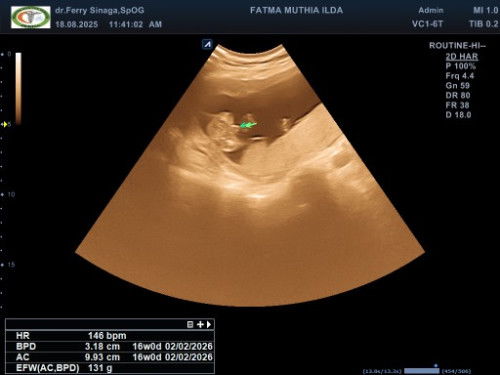

Aku baru aja USG bun di usia 20w dan alhamdulillah udah keliatan JK nya, sebenarnya udah ketara dari usia 17w cuman dokter nya masih belum yakin kemarin. Sekarang udah keliatan jelas banget tadi hasil USG nya. Tapi kata dokter tergantung kondisi perkembangan janinnya juga soal hasil JK nya.

16 mnggu sudah jelas bun